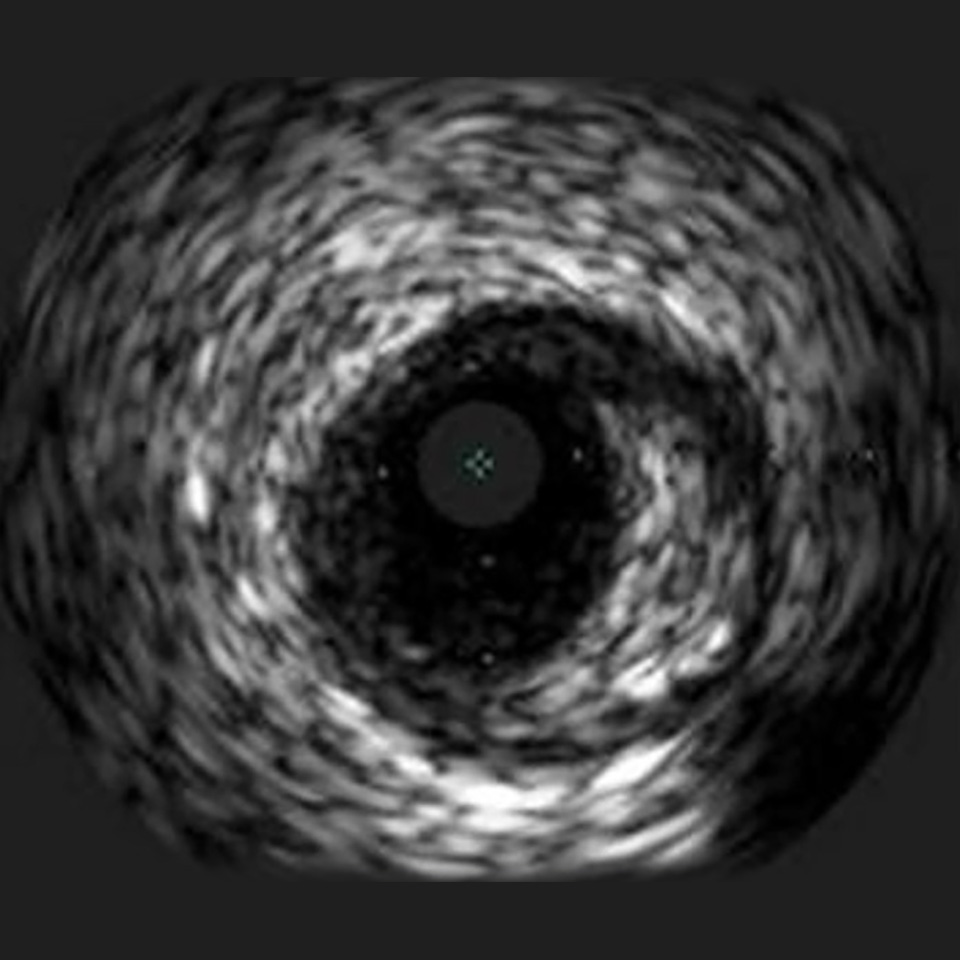

OPTICROSS Imaging Catheter 40 MHz

IVUS image of inside a coronary vessel using the 40MHz Opticross catheter

Axial resolution: 38 µm